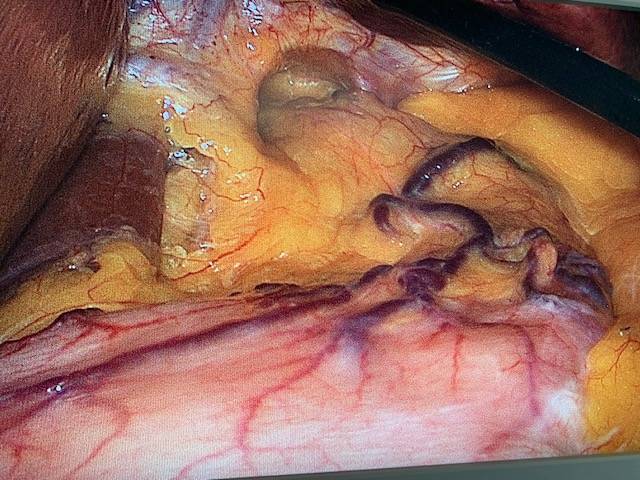

Traitement chirurgical des hernies internes après bypass en Y: une Expertise du groupe MUST à Paris

La hernie interne (HI) fait partie des complications chroniques les plus fréquentes après bypass gastrique en Y (BPGY). L’incidence de cette complication dép...